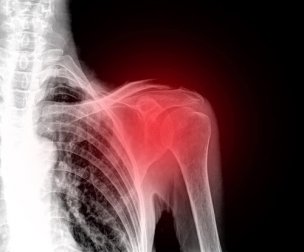

Il existe différents types de lésions à l’origine des douleurs à l’épaule, des inflammations et de l’incapacité de bouger. L’inflammation peut devenir chronique si elle n’est pas traitée à temps.

Les douleurs à l’épaule sont plus fréquentes que vous ne le pensez et, surtout, elles ont une solution. Il est parfois nécessaire de consulter un médecin, notamment en cas de luxation ou fracture. Ces deux situations sont généralement dues à de graves traumatismes dans cette zone.

Les pathologies les plus courantes liées à la douleur de l’épaule sont les suivantes :